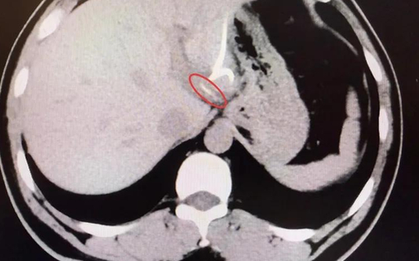

Các triệu chứng ban đầu của ung thư gan thường rất mờ nhạt, dễ nhầm lẫn với dấu hiệu mệt mỏi thông thường. Điều đó khiến nhiều người phát hiện bệnh khi đã ở giai đoạn muộn.